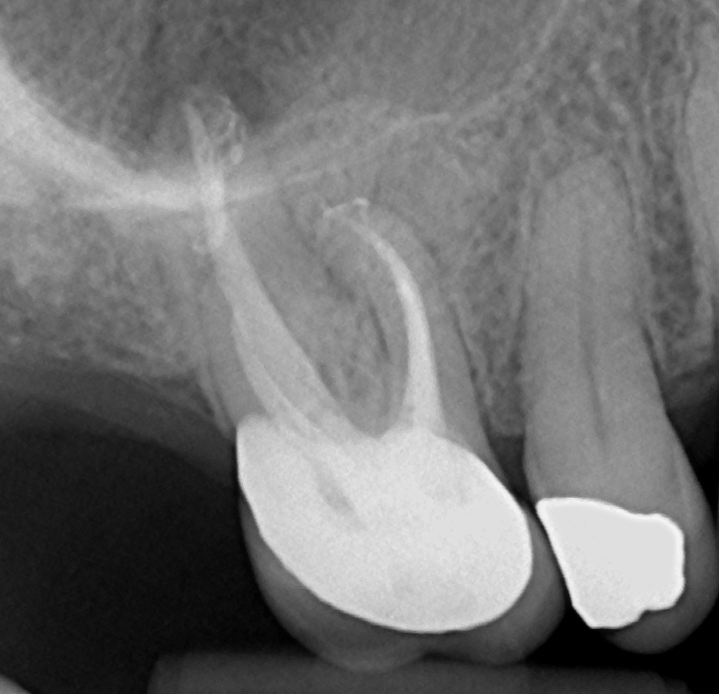

Well that was fun!🤣 UR6 RCT always cautious when negotiating a dog-leg curvature in this case MB1 and MB2. High risk of file separation #savingteeth #endodontics